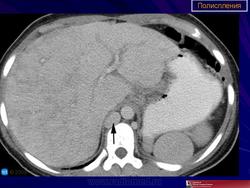

Полиспления

ID: 18841 Polysplenia syndrome Dr Ian Bickle - 24 Jul 2012 Features of polysplenia syndrome (aka left sidedness or left isomerism) ...

ID: 12761 Polysplenia syndrome , situs ambiguous, rectal mass Dr Amro Nazih Omar - 7 Jan 2011 Axial CECT demonstrates polysplenia, situs ambiguous, absent IVC an...